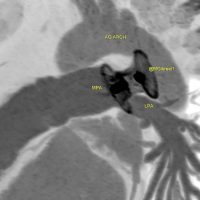

19m baby post trans-catheter PDA closure. [gallery ids="16649,16652"] Echo >>aliasing across LPA. these two images can tell alot Mohamed Gibreel , FEBR (Fellowship of Egyptian Board of Radiology ) Cardiac..